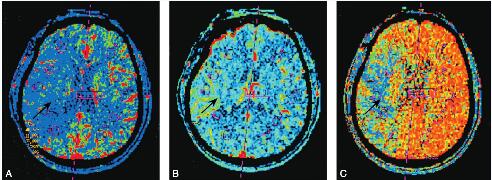

颅脑CT灌注成像(CT perfusion,CTP)(2010年1月7日)提示右侧大脑半球梗死区周围局部脑血流量(regional cerebral blood flow,rCBF)明显减少,脑血容量(cerebral blood volume,CBV)正常,对比剂平均通过时间(mean transmit time,MTT)明显延长(图1.5-4)。

图4 颅脑CTP

A.右侧大脑半球梗死区周围rCBF明显减少;B.CBV正常;C.MTT明显延长(黑箭头)

本例患者为老年男性,合并糖尿病、高血压等基础疾病,CT提示右侧分水岭梗死,CTP提示梗死区周围大片低灌注区,表现为CBF降低、MTT延长、CBV无明显变化,与文献报道的慢性缺血区CT灌注情况一致[8],MTT延长、CBV无变化提示侧支循环建立,但侧支循环中小血管、毛细血管未出现代偿性扩张,故术后发生高灌注出血可能性不大。患者反复出现颈动脉系TIA发作,提示侧支循环代偿功能不足,梗死面积扩大的可能性增加。有报道显示,如不及时干预,此类患者发生完全性卒中的几率明显增高,其发作后2天内卒中风险超过5%,3个月内卒中风险为8.3%~10.7%,1年内卒中风险为12.8%~16.2%[9,10]。因此,该患者进行右侧大脑中动脉血管再通手术适应证明确,术后CTP、CTA提示血管通畅,MTT、CBF、CBV恢复正常,无高灌注出血,但出现左下肢肌力下降,CT示右侧大脑半球侧脑室旁新发梗死灶,考虑为球囊扩张过程中大脑中动脉深穿支血管豆纹动脉闭塞。